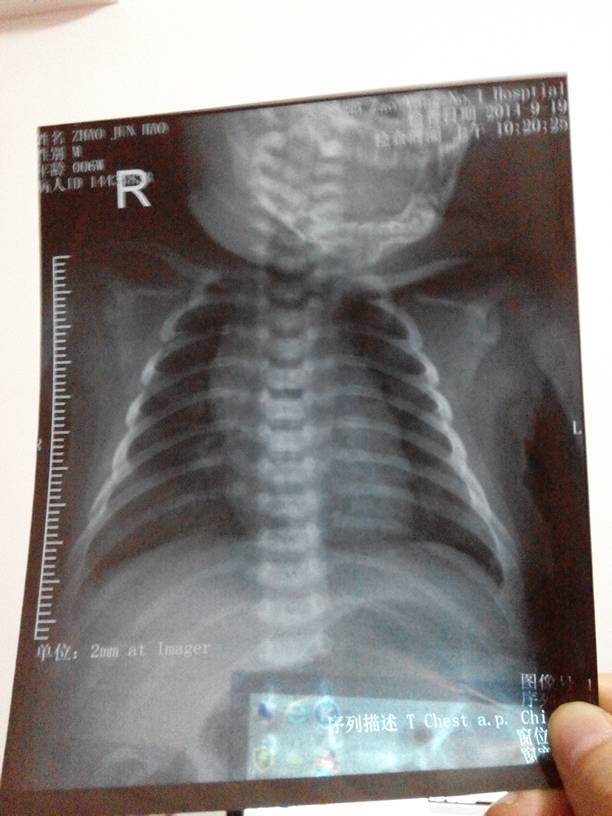

哪位医生能帮我看下我们家宝宝的x光片,肺部情况! 哪位医生能帮我看下我们家宝宝的x光片,肺部情况! 点击展开 @浩浩 2014-09-19 19:42 相关问题 请问我家宝宝35天了,之前在月子里就感冒了,后来又去医院检查,医生给拍了肺部的ct,小孩那么小,那 宝宝还那么小,就得了肺部炎症,听医生说好严重,说得我好担心,希望宝宝快点好起来 有医生在吗?可以帮下我嘛,我宝宝肺炎才出院医生说肺部听的是好的,可是回来咳的厉害喉咙还有痰鼻子不通